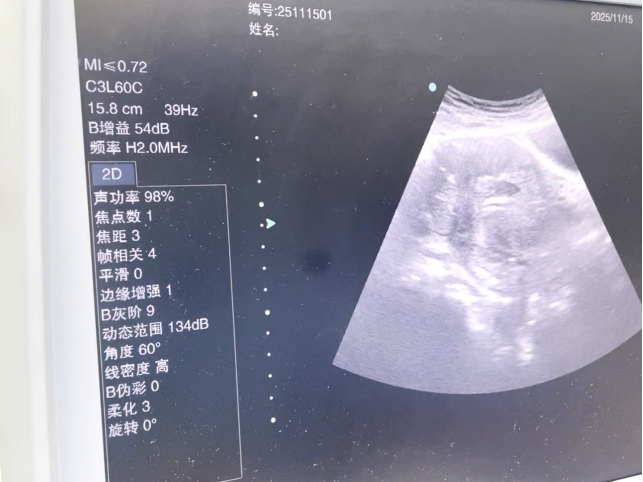

杨冰主任进一步说明:“射频消融技术是在影像引导下,将消融电极精准置入肌瘤内部,通过热能使其发生凝固坏死,终被机体逐渐吸收。该技术具有创伤小、恢复快、保留器官功能完整等优势。”

通过射频消融术,十年肌瘤一朝解除

在完善术前准备后,手术由杨冰主任主导操作,杨春花主任协同配合。术中,专家团队凭借丰富经验,精准定位肌瘤位置,将消融电极置入病灶中心区域,实时监控消融范围,确保肌瘤组织被有效灭活的同时,不对周围正常组织造成损伤。